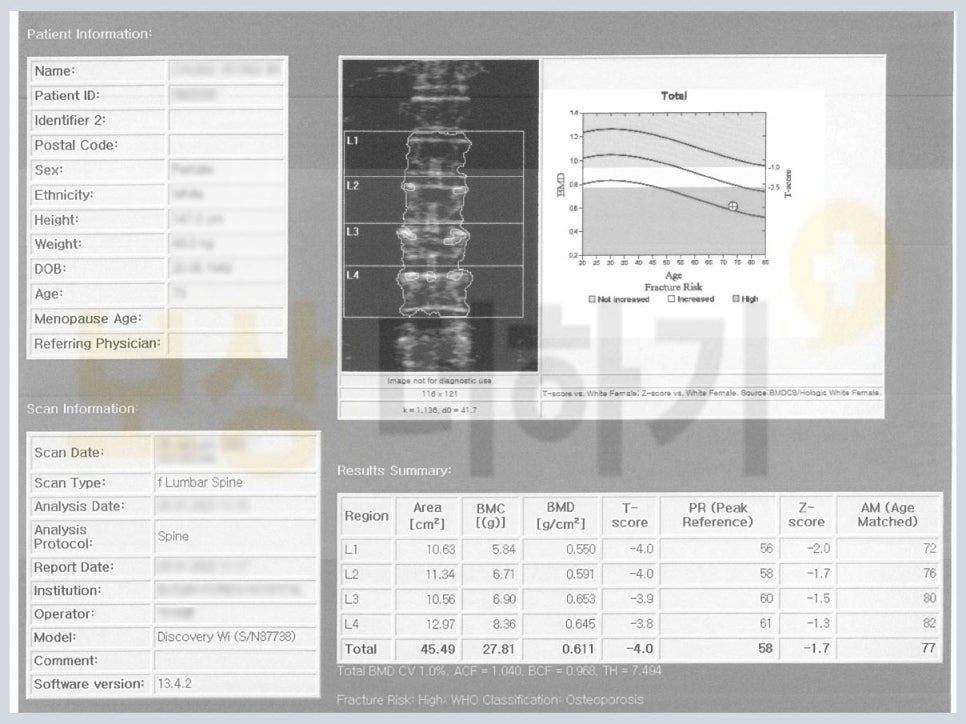

골밀도 검사를 했을 때 그 결과를 숫자로 나타내며 이를 T-score(티 스코어)라고 합니다. 숫자가 마이너스로 커질수록 골밀도가 낮은 것입니다. ▲ 정상ː-1.0 이상 ▲ 골감소증ː-1.0 에서 -2.5 사이 ▲ 골다공증ː-2.5 이하

골밀도 검사 T 스코어: 마이너스 4

이와 같이 골다공증이 있는 분들은 그렇지 않은 분들에 비해 골절이 발생할 가능성이 높습니다. 보험사는 이러한 기왕증이 신체에 영향을 미친 부분만큼 감액하려 합니다.